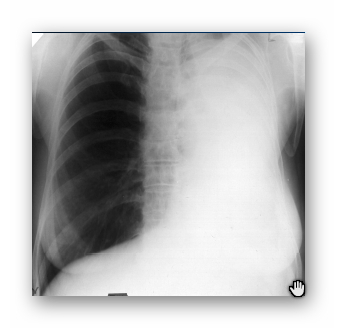

NIEDODMA PŁUCA LEWEGO

RTG

(WTÓRNA DO RAKA CENTRALNEGO PŁUCA LEWEGO)